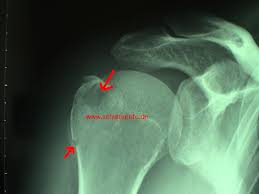

Schulter gebrochen ohne op. Der Bruch des Schlüsselbeins ist eine häufige Sportverletzung. Bestehen nach einem Unfall starke Schmerzen im Bereich der Schulter kann dies ein Hinweis auf eine Humeruskopffraktur sein. Eine Operation ist auch notwendig wenn die Schulter immer wieder ausrenkt.

Ob man sich die Schulter gebrochen hat wird man als Betroffener recht schnell bemerken da man starke Schmerzen in der Schulter hat und die Bewegungsfreiheit stark eingeschränkt ist. Arm und Schulter können nicht wie ursprünglich bewegt werden. Weiteres Anzeichen für einen solchen Bruch ist die Unfähigkeit den Arm oder die Schulter zu bewegen.

Ein Schulterbruch verursacht meist starke Schmerzen und Bewegungseinschränkungen. Folgende Komplikationen können im Zusammenhang mit der Operation entstehen. Der Bereich ist meist geschwollen und druckschmerzhaft.

Der Bruch des Schlüsselbeins ist eine häufige Sportverletzung. Ist es beim Unfall zu einer erheblichen Verschiebung der Knochenfragmente gekommen sind die Chancen auf ein gutes Ausheilen und Wiedergewinnen der Schulterfunktion ohne Operation schlecht. Während die Verletzung in der Vergangenheit fast ausschließlich konservativ also ohne Operation behandelt wurde erfolgt. Eine Schultersteife Frozen shoulder mit mehr oder weniger ausgeprägten Bewegungseinschränkung der Schulter und des betroffenen Armes ist mit und ohne Operation - manchmal zu beobachten. Auch das kann nur das MRT zeigen. Arm und Schulter können nicht wie ursprünglich bewegt werden. Implantat versagt bricht oder wandert. Etwa 85 Prozent der Brüche können ohne Operation behandelt werden. Nach Ruhigstellung von fünf bis sieben Tagen Dauer in einem speziellen Verband erfolgt die Übungsbehandlung zunächst noch ohne Belastung ab der siebenten Woche nach dem Unfall wird zunehmend belastet.

Weiteres Anzeichen für einen solchen Bruch ist die Unfähigkeit den Arm oder die Schulter zu bewegen. Eine Schultersteife Frozen shoulder mit mehr oder weniger ausgeprägten Bewegungseinschränkung der Schulter und des betroffenen Armes ist mit und ohne Operation - manchmal zu beobachten. Nach Ruhigstellung von fünf bis sieben Tagen Dauer in einem speziellen Verband erfolgt die Übungsbehandlung zunächst noch ohne Belastung ab der siebenten Woche nach dem Unfall wird zunehmend belastet. Der Bruch des Schlüsselbeins ist eine häufige Sportverletzung. Etwa 85 Prozent der Brüche können ohne Operation behandelt werden. Eine Operation geht immer mit gewissen Risiken einher wie zum Beispiel Entzündungen. Implantat versagt bricht oder wandert.